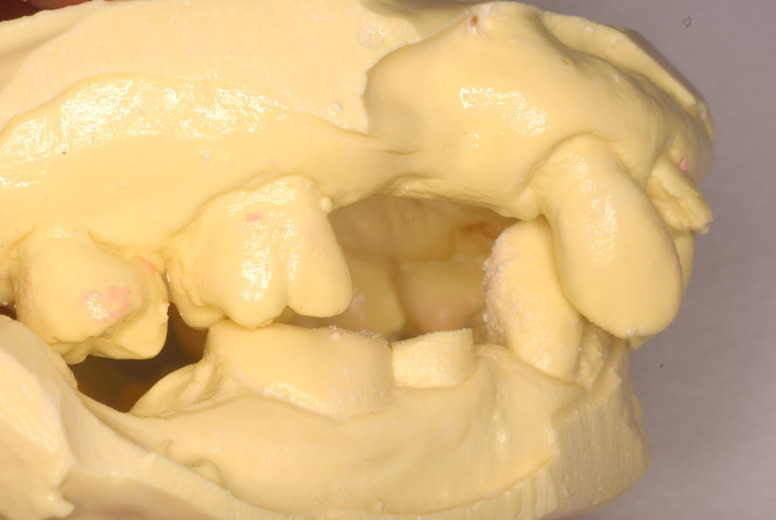

写真左下の親知らずが痛くなり抜歯しました。その後歯茎を除去して虫歯を露出させる処置を二回ほどしています。

レントゲンでは小さいですが、こう言う虫歯が一番怖いのです。

治療の成功率は極めて悪くすぐ再発しやすいのです。